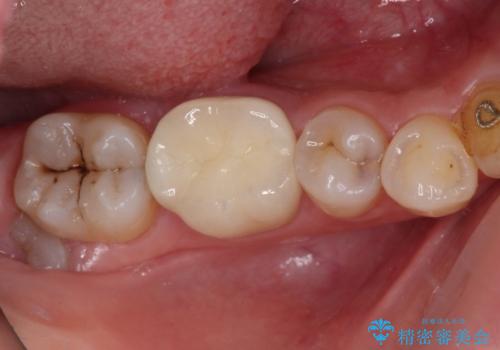

速やかにラバーダム下にて根管治療を行うこととし、その後オールセラミッククラウンにて補綴治療を行うこととしました。

治療期間中、痛みが生じることはなく、処置後3か月経過しましたが良好な状態を保っています。